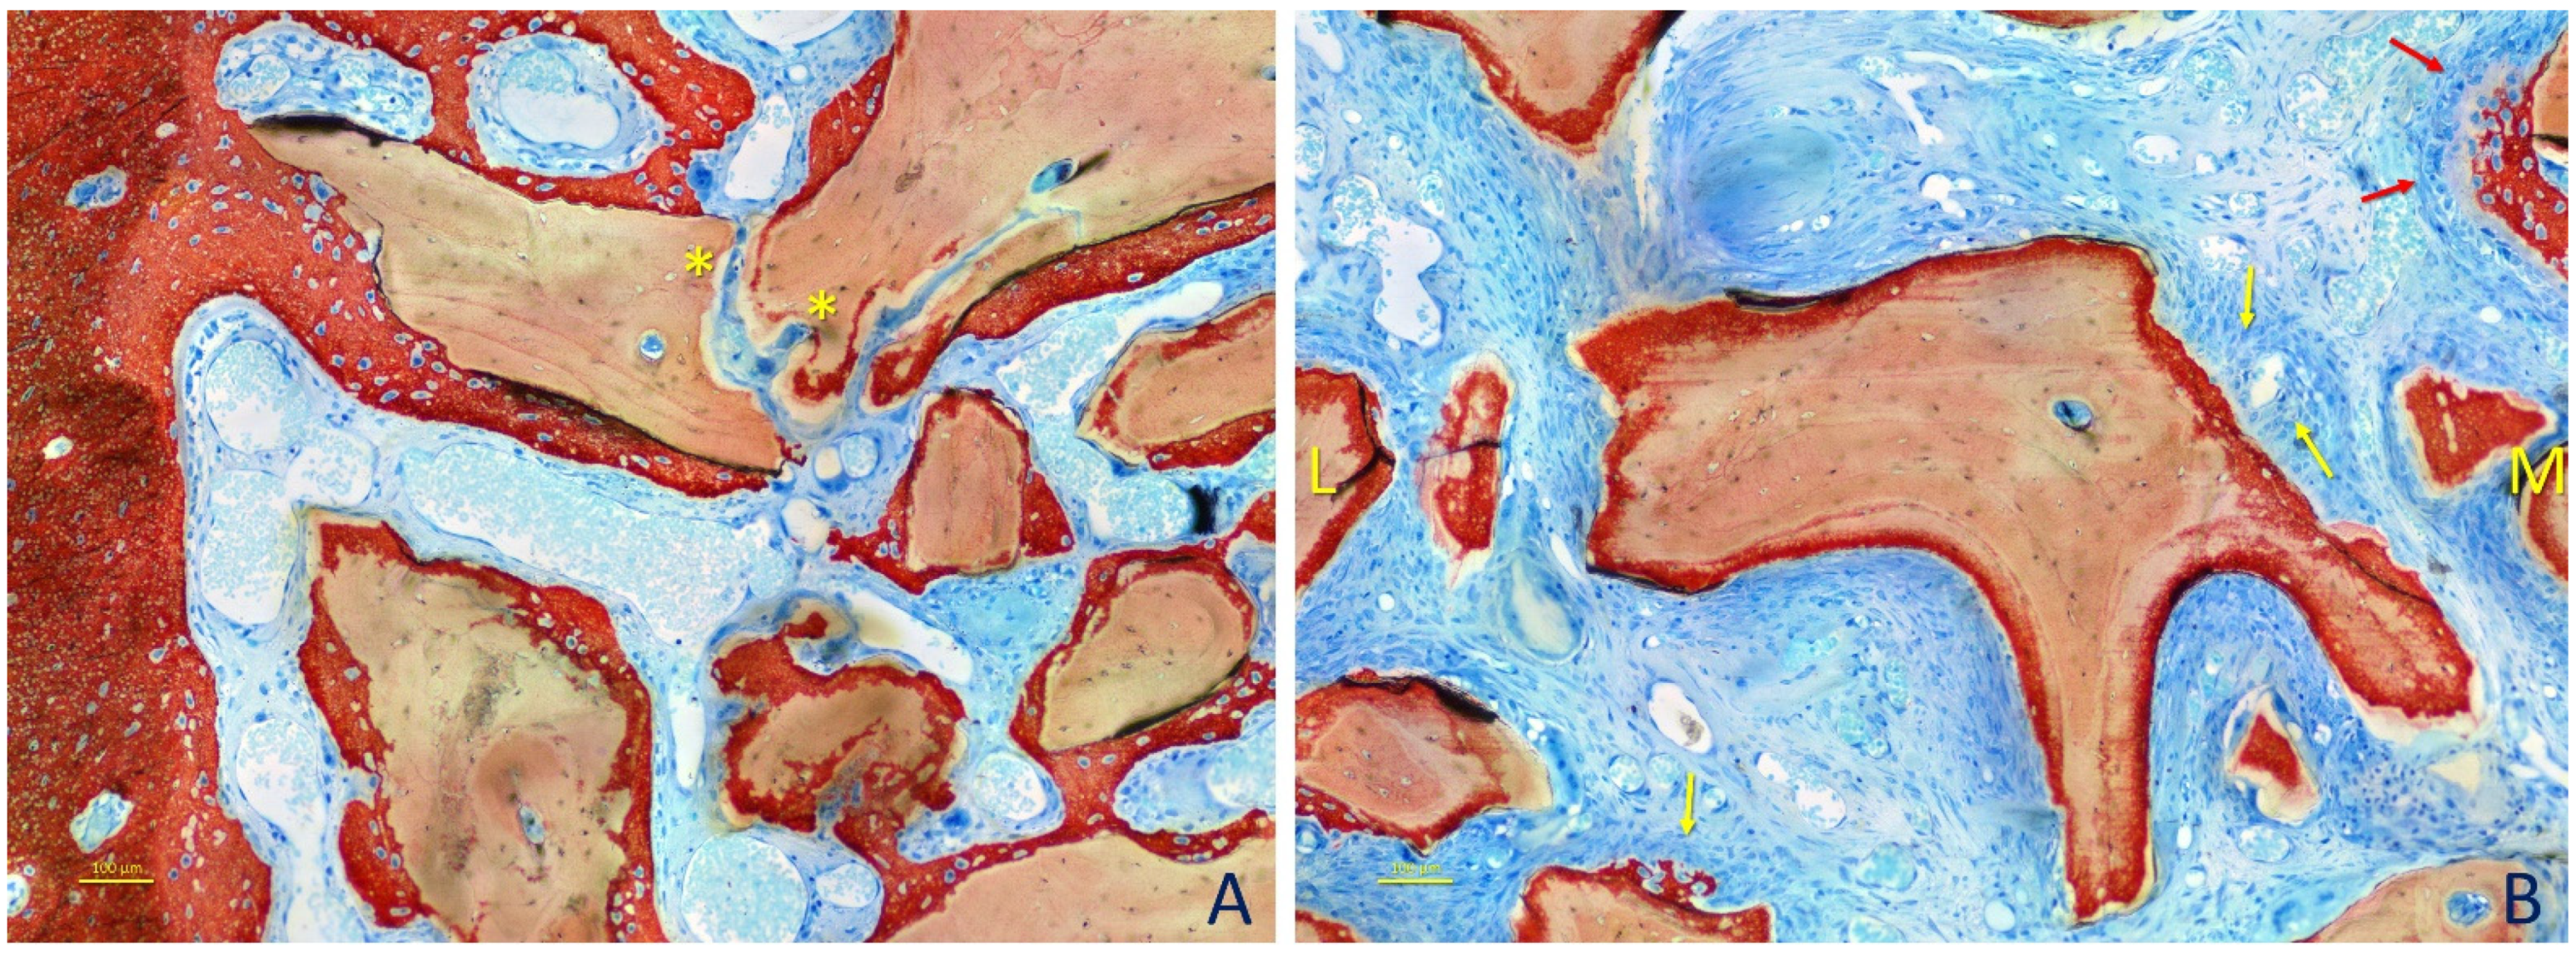

3. Results